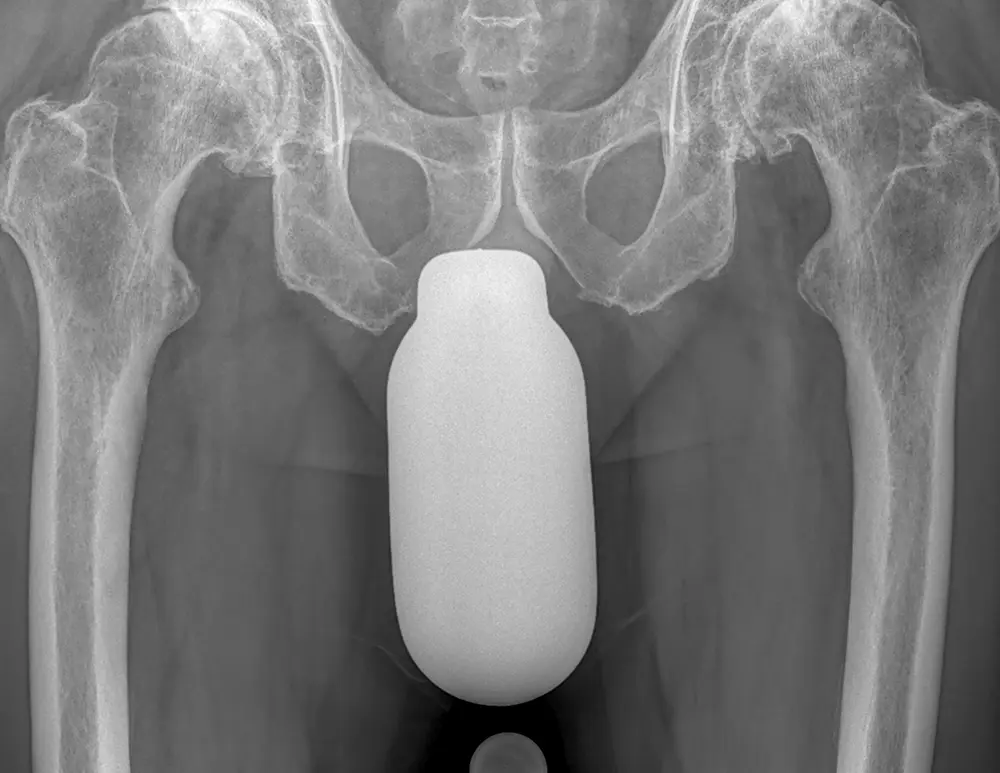

Die gleichzeitige beidseitige Implantation von Hüftprothesen

Die gleichzeitige beidseitige Implantation von Hüftprothesen wird in vielen Ländern, z. B. den USA, häufig durchgeführt, ist jedoch in Deutschland noch relativ selten. Prof. Dr. Hans Gollwitzer und Prof. Dr. Patrick Weber diskutieren im Interview für den Berufsverband für Orthopädie und Unfallchirurgie die Vorund Nachteile der simultanen beidseitigen Hüftendoprothetik und stellen zwei Fallbeispiele vor.

Anhand von zwei Kasuistiken werden die breiten Einsatzmöglichkeiten der simultanen beidseitigen Implantation von Hüfttotalendoprothesen aufgezeigt: